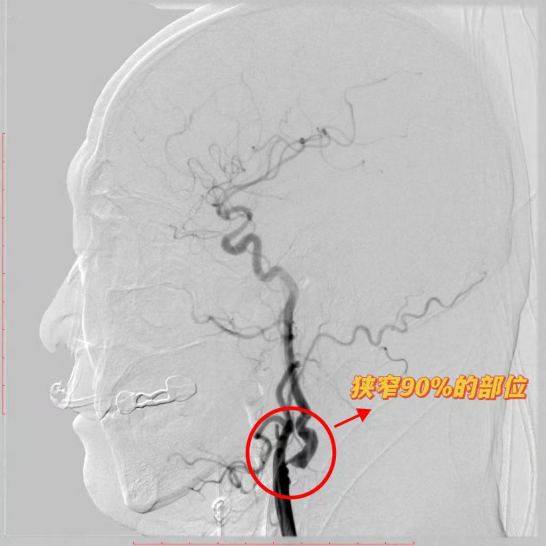

济南南郊医院脑科急性脑梗取栓 从发病到血管开通一气呵成 彰显硬核救治实力

前几日的一个晚上8点多,张女士(化名)家中却乱作一团——她突然说不出话,端着水杯却喝不到水。家人慌忙拨打120,救护车将她送进济南南郊医院急诊科。